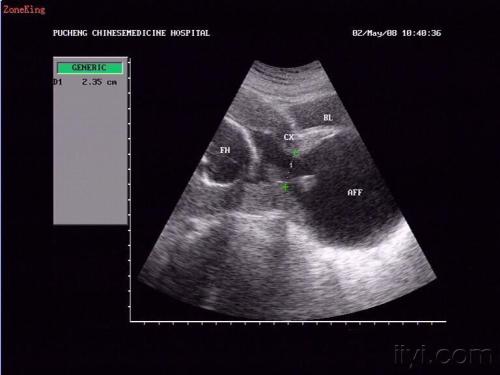

但是,过了半个月,小汪又出现在了急诊室,检查发现,小汪的羊膜囊再次突出于宫颈外口,大小约3x3cm,B超也显示宫颈管分离,腹中胎儿再次面临流产的风险。

我们都清楚,这在临床上属于难免流产,也就是说,孩子保不住了。